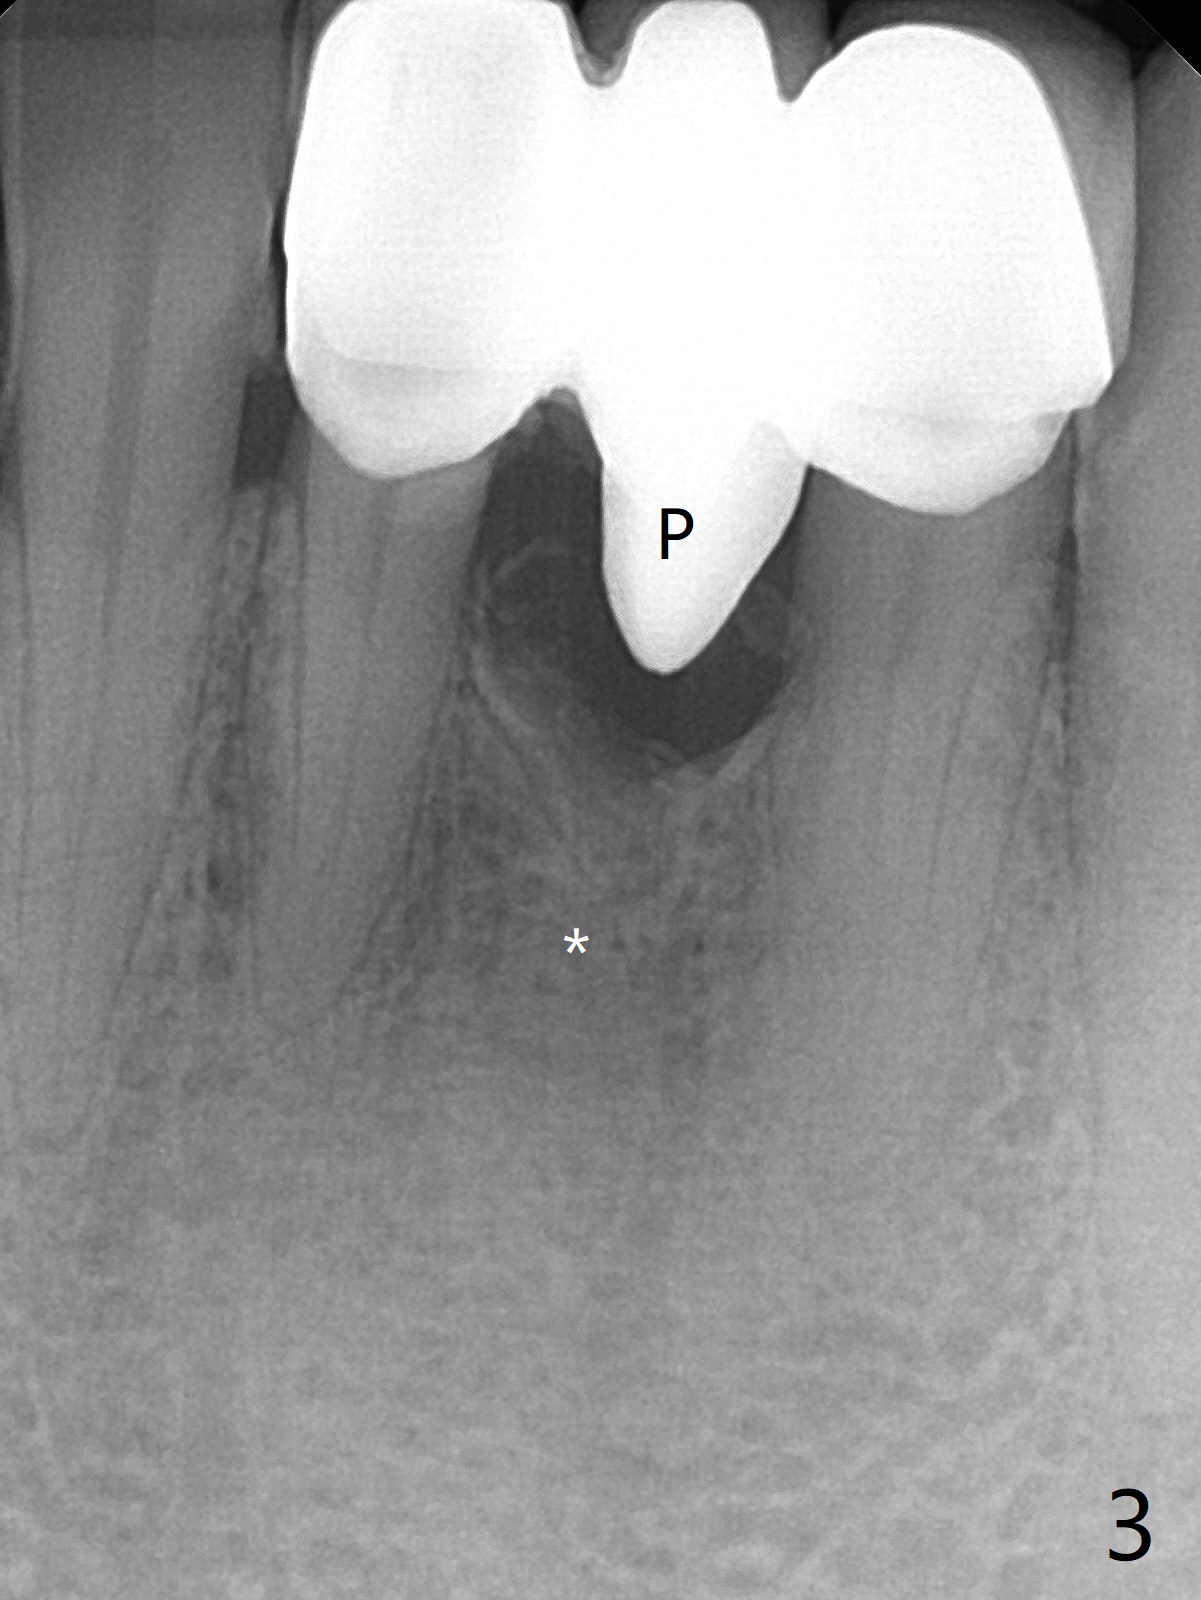

A 38-year-old man has gingival erythema and edema associated with #23-25 bridge (Fig.1). The most abnormal finding is the long pink porcelain at the pontic (Fig.2, 3: P). After taking Alginate for future provisional, the bridge is removed. The edentulous ridge must be atrophic, as shown in low density (Fig.3: *). A 2.0 mm 1-piece implant is proper for the site, as will be shown by CT. In fact 2.5 mm one is proper (Fig.4). The gingival erythema reduces significantly post bridge removal, SRP and water pik. After incision, surgical handpiece and diamond round bur are used to flatten the ridge until 4 mm.